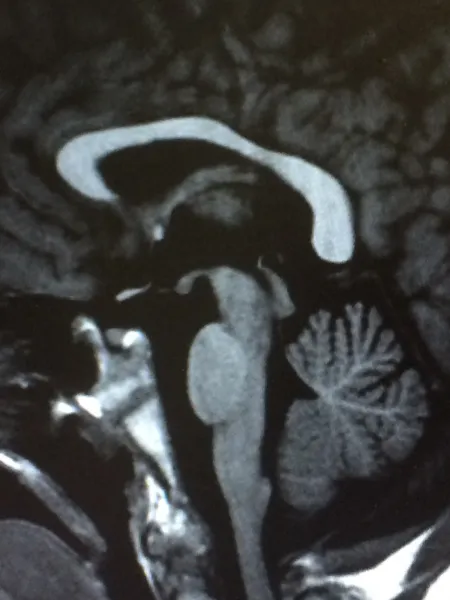

Discover a parent's experience with Young Epilepsy's diagnostic EEG services, accessible through NHS referrals or for private patients. Consult your healthcare provider for details.